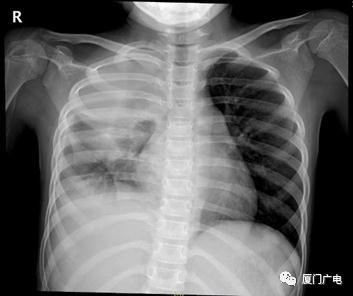

收治了一名大量胸水的患兒

8歲的妍妍因高熱、氣急就診

完善檢查發現大量胸腔積液

入院立即行胸腔穿刺術

抽取胸水檢出牙齦卟啉單胞菌

給予抗感染以及后續胸腔廓清手術治療

患兒病情好轉